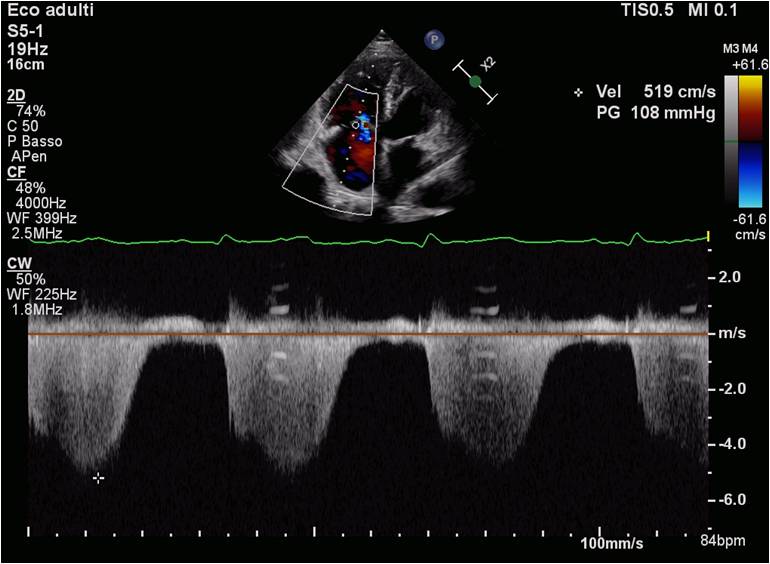

Introduction Idiopathic pulmonary arterial hypertension (IPAH) is a rare and progressive disease characterized by elevated pulmonary arterial pressure in the absence of identifiable causes, leading to increased vascular resistance and right ventricular overload. Early diagnosis and targeted therapy are critical for improving prognosis (1). Clinical case A 46-year-old female came to our attention for worsening episodes of syncope and dyspnea (NYHA III). Echocardiogram revealed moderate tricuspid regurgitation, PAPs 108 mmHg, right heart dilation, TAPSE 16 mm, atrial septal aneurysm and suspected patent foramen ovale (PFO). A dynamic test for right-to-left shunt revealed a mild shunt. NT-proBNP was 680 pg/ml. Myocardial perfusion imaging, spirometry, abdominal ultrasound, HIV tests, autoimmune panel and videocapillaroscopy were normal. Ventilation-perfusion scintigraphy showed areas of hypoperfusion but computerized tomography excluded thromboembolic form. Right heart catheterization showed a mean pulmonary pressure of 48 mmHg, a wedge pressure of 10 mmHg and vascular resistances (PVR) of 12.2 WU. According to ESC guidelines PFO wasn’t closed and, given the high PVR, we concluded with a diagnosis of IPAH with incidental finding of PFO. During 6-minute walk test (6MWT) the patient covered 320 meters with desaturation. This was integrated with NT-proBNP, clinical, echocardiographic (TAPSE/PAPs 0.16, RA area 19 cm², absence of pericardial effusion) and hemodynamic parameters (RAP 6 mmHg, CI 1.8 L/min/m², SVI 20 mL/m²), concluding with an intermediate risk. We opted for an upfront combination therapy. The patient showed significant improvement in NYHA class (I-II) and no more syncope. NT-proBNP was reduced to 265 pg/ml and she covered 452 meters without desaturation. The patient's risk profile had dropped to low risk. However, she still had PAPs of 65 mmHg and needed a major bilateral hystero-oophorectomy so we added a third drug with subsequent substantial reduction in PAPs. Conclusion In these high-risk patients we must not limit ourselves to NYHA class and functional capacity. Guidelines state that PAH patients are at high risk of right heart failure and death. Therefore they recommend therapeutic optimization before surgery. References Humbert M, Kovacs G, Hoeper MM, et al. 2022 ESC/ERS guidelines for the diagnosis and treatment of pulmonary hypertension. Eur Heart J. 2022 Oct 11;43 (38):3618-731.